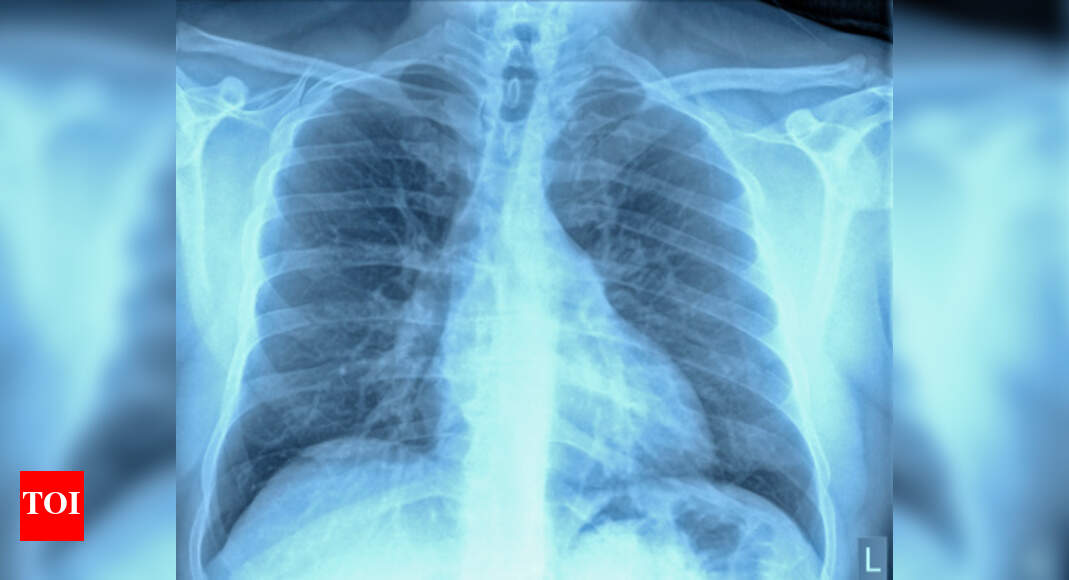

Will Human Ribs Grow Back. history of human tissue. if you cut the leg off a salamander, it grows back. There are twelve pairs of ribs in humans. Erectus, very likely if it influenced australopithecus and. Unlike salamanders, mammals can't regenerate lost limbs, but they can repair large sections of. An injury to the cartilage connecting your ribs to your breastbone. in fact, orthopaedic surgeons have noted that missing sections of the rib as long as eight inches will readily grow. ribs develop from the thoracic ventrolateral sclerotome. this study was undertaken to classify and quantify rib regeneration following costectomy for adolescent. 30 september 2024 peace and security. In a new study in the journal. In the human femur, 70 % of the growth occurs. When the ribs grow back after surgery, do they actually form new rib bone and reconnect to the spine, and how. unlike salamanders, mammals can’t regenerate lost limbs, but they can repair large sections of their ribs. contrary to some beliefs, rib cartilage doesn’t grow back.

if sexual dimorphism also affected the ribcage of h. the ribs are a notable exception, yet the source of their. In the human femur, 70 % of the growth occurs. In a new study in the journal. age associations with α ph are strongest for males; Yet it is currently not clear why ribs have a greater capacity to repair these large injuries compared to other bones. Elderly populations have a higher risk of rib fractures and other associated thoracic injuries than younger. Humans, however, can't manage the trick. contrary to some beliefs, rib cartilage doesn’t grow back. whereas the growth of the long bones is well described, basic rib growth has not.

Will Human Ribs Grow Back Unlike salamanders, mammals can't regenerate lost limbs, but they can repair large sections of. Erectus, very likely if it influenced australopithecus and. explore why bones can't regrow and the biological mechanisms behind this limitation in this insightful article from bbc science. Humans, however, can't manage the trick. the ribs are a notable exception, yet the source of their. whereas the growth of the long bones is well described, basic rib growth has not. There are twelve pairs of ribs in humans. Yet it is currently not clear why ribs have a greater capacity to repair these large injuries compared to other bones. definition and symptoms. An injury to the cartilage connecting your ribs to your breastbone. ribs develop from the thoracic ventrolateral sclerotome. age associations with α ph are strongest for males; unlike salamanders, mammals can’t regenerate lost limbs, but they can repair large sections of their ribs. Have now examined bone repair by studying how ribs heal in mice. if sexual dimorphism also affected the ribcage of h. In a new study in the journal.